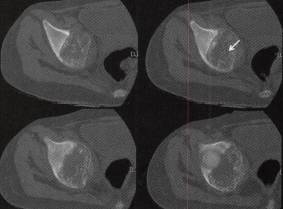

图1右盆骨软骨母细胞瘤

B

C

D

B〜D.CT骨窗见髋曰弥漫性溶骨性骨质破坏、骨皮质缺失及骨嵴,轻度骨膨胀,病灶边缘未见明显硬化